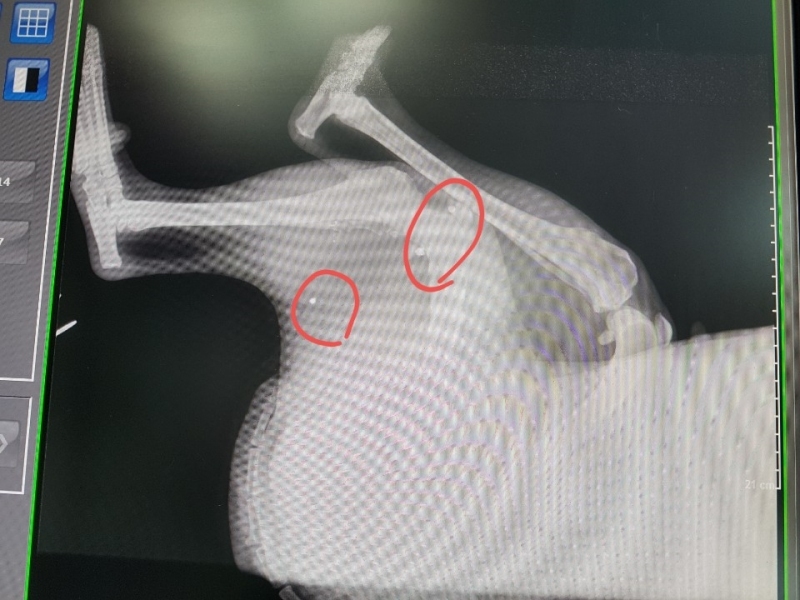

¿À´Ã ¼º³²¿¡ Àִ µ¿¹°º´¿ø¿¡ °¡¼­ ¿¢½º·¹À̸¦ Âï¾îº» °á°ú

½ÇźÀÌ ¿©·¯¹ß ¹ÚÇôÀִµ¥  ¼ö¼úÀ» ¸øÇÏ°í ¸Ô´Â°ÍÀº Àß ¸ÔÀ¸´Ï

°ßÀÌ ¸Ô´Â°Íµµ À߸԰í Ȱ¹ßÇѵ¥  ¿ÞÂÊ ¹ß¸ñÀ» ¾²Áö ¸øÇÕ´Ï´Ù,

¿ÞÂÊ´Ù¸® ¹ß¸ñ¿¡ ½ÇźÀÌ ¹ÚÇôÀִµ¥ »À¸¦ ¸Â°í ½ÇźÀÌ ºÎ¼­Áø ´À³¦ÀÔ´Ï´Ù,

±×ÂÊÀº Àε¥°¡ Àִµ¥  Àε¥°¡ ²÷¾îÁø°Í  °°¾Æ¿ä,

2¿ù 15ÀÏ ±¤Áֽà ÃÊ¿ù¸é¿¡ ÀÖ´Â À̼ٵ¿¹° º´¿ø¿¡¼­ Á¤¹Ð ¿¢½º·¹ÀÌ ÃÔ¿µ ÇßÀ¾´Ï´Ù,

´Ù¸®¿¡ ºÎ¼­Áø ¿±ÅºÀº »À¿¡ ¸Â¾Æ »À°¡ ±ÝÀ̰¡°í ¾à°£Àº »À¼ÓÀ¸·Î µé¾î °¬´Âµ¥

ºÎ¼­Áø ¿±ÅºÀ» »©´Â ¼ö¼úÀº ºÒ°¡´ÉÇÏ°í µ¿¹°Àº »ç¶÷ÇÏ°í ´Þ¸® ÀÌ»óÇÑ ¹°Ã¼°¡ µé¾î¿À¸é

Ç×ü°¡ »ý°Ü¼­ ¹°Ã¼¸¦ ¿¡¿ö½×°í ¸·ÀÌ »ý°Ü  ´õ´Â ÀÌ»óÀÌ ¾ø°í »ç´Âµ¥´Â ÁöÀåÀÌ ¾ø´Ù°í ÇϽôõ±º¿ä.

¿±ÅºÀÌ ½ÉÀå, Æó, ³»Àå±îÁö µé¾î°¡¸é À§ÇèÇѵ¥ ¸ö¼Ó¿¡ ¹ÛÈù°ÍÀº

¸Ô±â¸¸ ÀßÇÏ¸é »ì¼ö ÀÖ°í 3ÁÖ ÈÄ¿£ °ÅÀÇ Á¤»ó±îÁö ¿À´Ï±î ½Ã°£À» °¡Áö°í

±â´Ù·Á º¸¶ó´Â  µ¿¹°º´¿ø¿øÀå´ÔÀÇ Á¾ÇÕÀûÀÎ ÆÇ´ÜÀÔ´Ï´Ù,